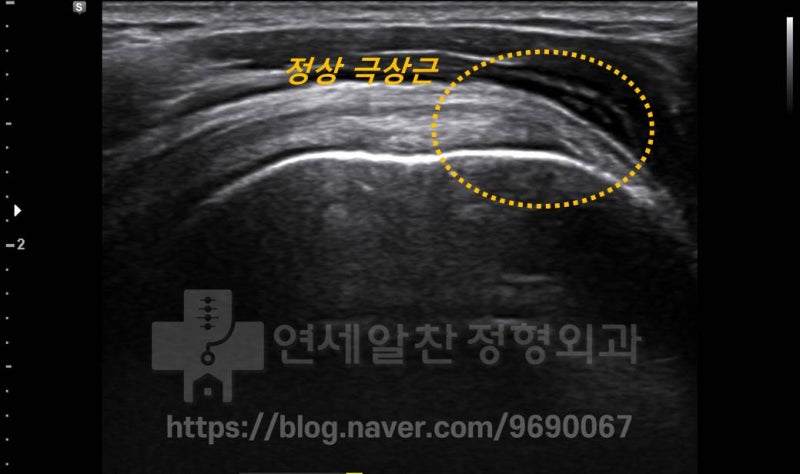

초음파에서 정상적인 극상근 부위를 관찰하였습니다. 둥근 점선 내로 정상적인 극상근의 형태가 관찰됩니다.

극상근 부위를 면밀히 관찰하면서 부분적으로 손상된 어깨회전근개파열을 확인할 수 있었습니다. 인대의 전체적인 모양이 유지되는 관절내측 또는 실질 부분 파열인 것으로 보입니다. 극상근의 단면 부위를 다시 한번 초음파로 살펴보았습니다.

노란 둥근 점선으로 표시된 부위가 어깨회전근개파열이 발생한 부위로 약간의 염증 소견은 보이나 정상적인 소견이 관찰됩니다.